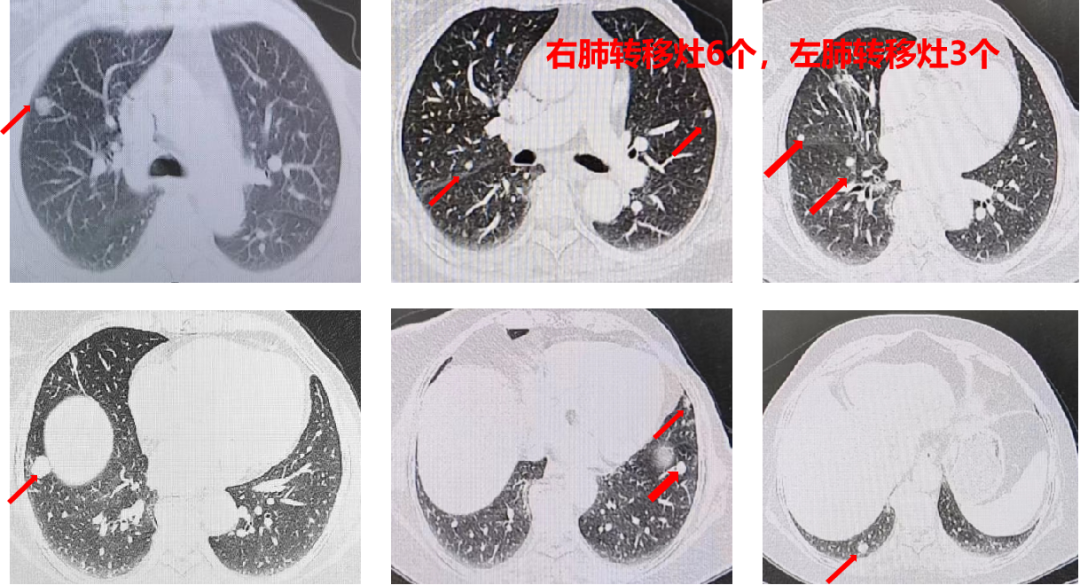

胸部+全腹部增强CT(我院 2021-02-17):直肠壁增厚,考虑直肠癌;盆腔多发稍大淋巴结;肝左叶低密度影,不除外转移瘤;双肺多发结节影,考虑转移瘤(左肺3个,右肺6个,较大者位于右肺下叶,直径约1.6cm)。

盆腔+上腹部增强MRI(我院 2021-02-20):肝左叶异常信号,考虑转移;双肺多发结节影。

直肠壁肿物,肿瘤矢状径:4.2cm;最厚处2.0cm;肿瘤远端距肛缘10.2cm,符合直肠癌表现(影像分期T4aN2Mx);盆腔多发增大淋巴结。